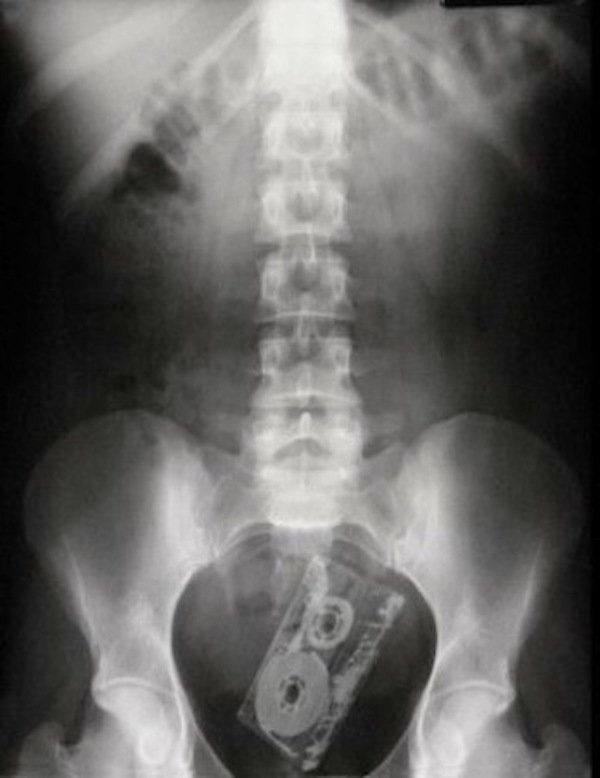

/ 15Kaseta mangetofonowa

Obraz

© imgur.com

Muzyki już z tego nie puści.